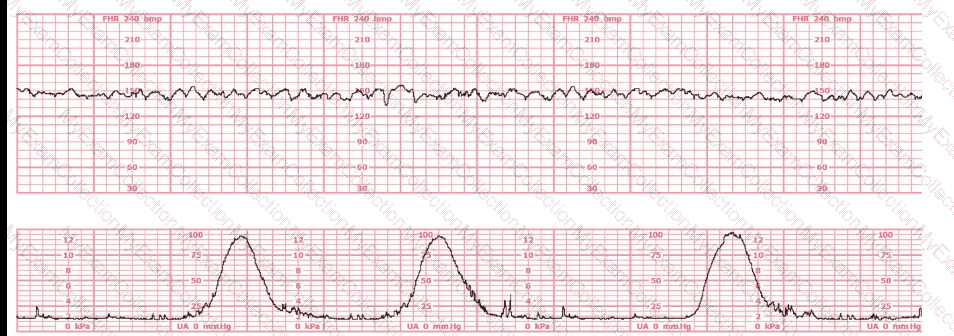

A woman is being induced with oxytocin. The tracing shown is representative of 20 minutes. Based on this tracing, the next step would be to:

A 30-year-old woman (G2P0) is experiencing preterm labor at 26-weeks gestation. She is receiving magnesium sulfate for neuroprotection. Her external fetal monitoring tracing over the past 30 minutes is shown. The next step would be to:

A woman in labor has been pushing for 4 hours. For the last 2 hours, there have been recurrent variable decelerations. Variability has evolved from moderate to minimal. Cervical exam is 10/100%/+2, fetal head OP. There has been no fetal descent for the last 45 minutes. Based on the tracing shown, the most reasonable approach is

The decelerations seen in the fetal monitoring tracing shown are best described as:

A woman has been 5 cm dilated for the past 3 hours. The tracing shown has developed over the last 30 minutes. The best initial course of action is to: